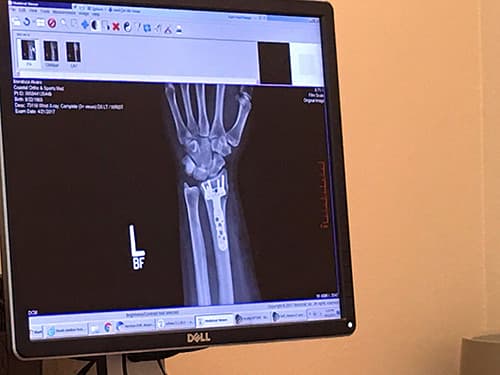

¿Diagnóstico médico? Fractura de la muñeca de la mano izquierda, con lesión de los ligamentos. Un incidente que, más allá de ser doloroso e incómodo, me obligó a pasar por el quirófano. El médico determinó que era necesario colocar algunos tornillos, y programó la cirugía para el martes 11 de abril. Mientras, pastillas para soportar el dolor y paciencia para la incomodidad.

La mano biónica: plaquetas y tornillos para fijar los huesos.